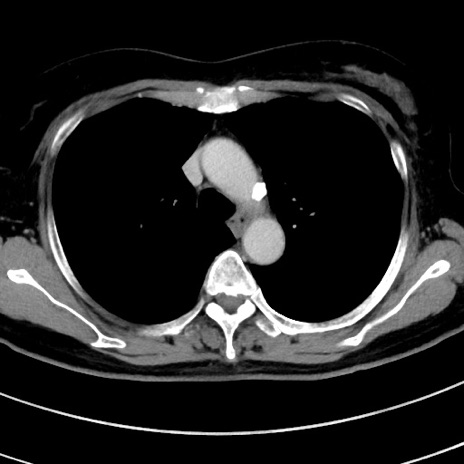

症例9(横断像)

【症例】 60歳代女性

【主訴】むかつき、みぞおちの痛み

【現病歴】3日前よりむかつきがあり、食事がとれない。

【既往歴】糖尿病

【身体所見】発熱なし、心窩部圧痛軽度あるも、腹膜刺激症状なし。

【データ】WBC 7400、CRP 1.92